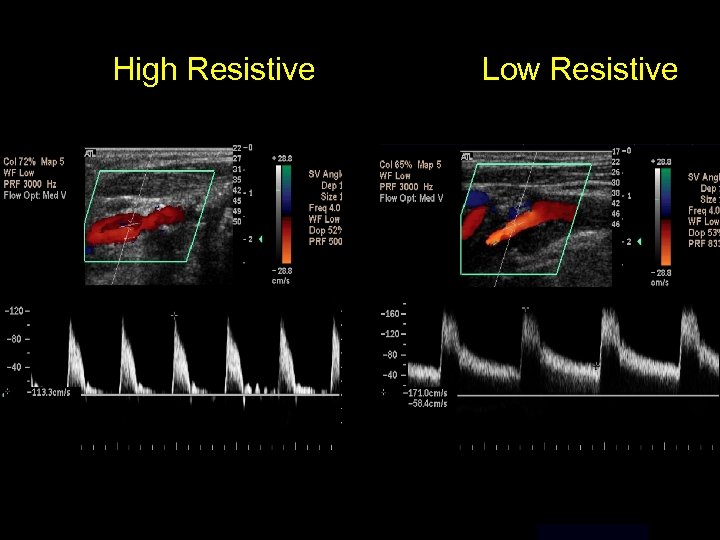

High Resistive Low Resistive